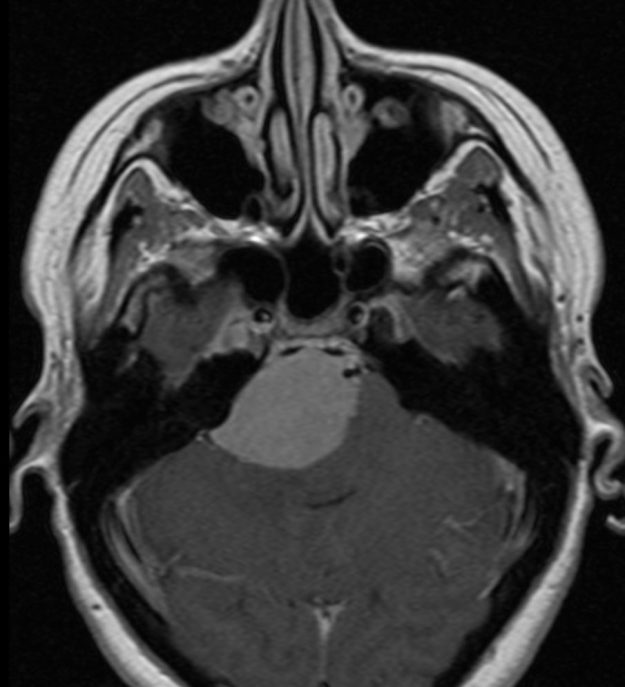

Μηνιγγίωμα περιοχής Επίφυσης

Ασθενής γυναίκα, 52 ετών η οποία παρουσίασε υπακουσία και επεισόδια πάρεσης του προσώπου. Ο απεικονιστικός έλεγχος με μαγνητική τομογραφία ανέδειξε ευμεγέθη όγκο στην περιοχή της επίφυσης (κωνάριο) με πίεση επί του μεσολοβίου, του τετραδύμου πετάλου και λοιπών εν’ τω βάθει δομών. Διενεργήθη δεξιά ινιακή, διασκηνιδιακή, διαδρεπανική προσπέλαση και ολική αφαίρεση της βλάβης. Η μετεγχειρητική αξονική…